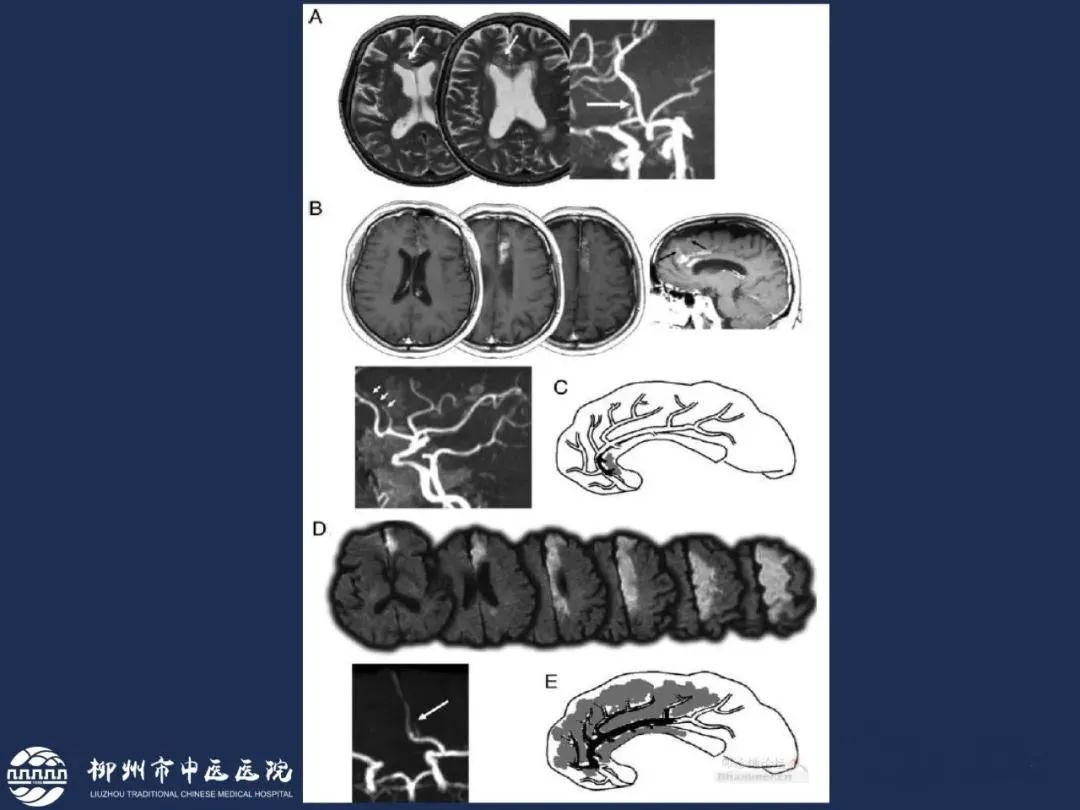

分水岭梗死皮质前型+皮质后型+后上型皮质下前型+皮质下后型+皮质下上型+皮质下外型+皮质下下型